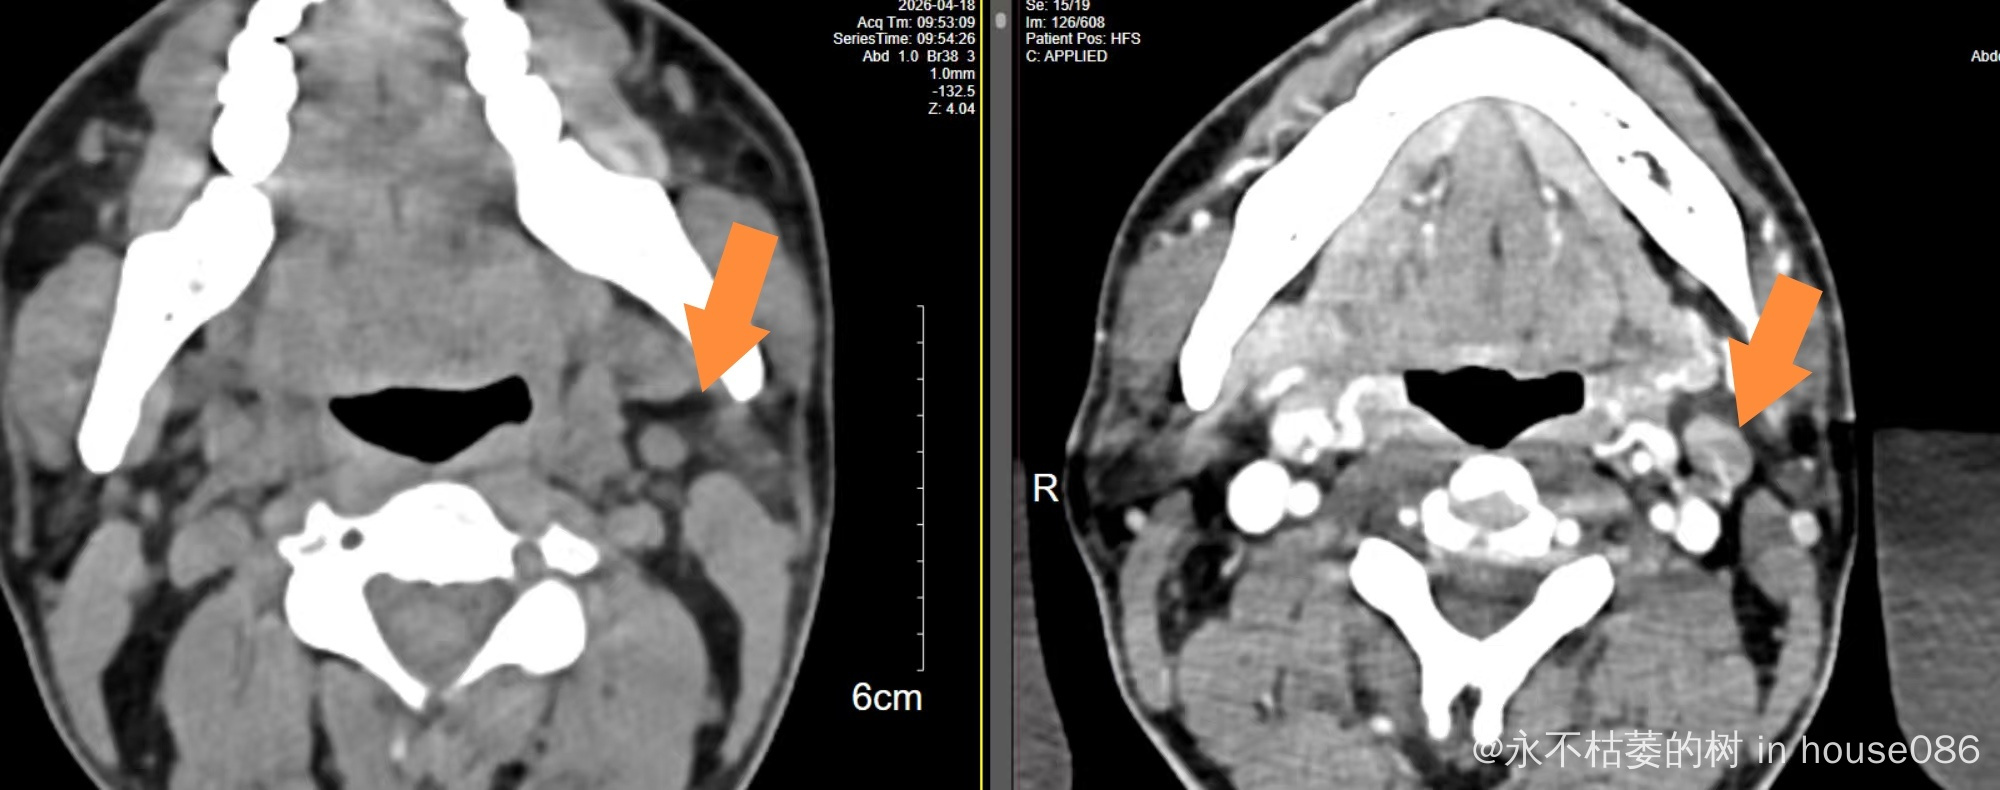

目前2周期化疗后第14天查白细胞低了,中性粒细胞0.6*10*9,打了两次短效升白针(隔天一次),第18天查恢复了,只是睡眠很差,常需要助眠药辅助睡眠,今日今日复查了颈胸腹部CT,大多数病灶都缩小了大概50-70%不等,我还是很欣慰,我是准备4周期后再做PETCT行中期评估。